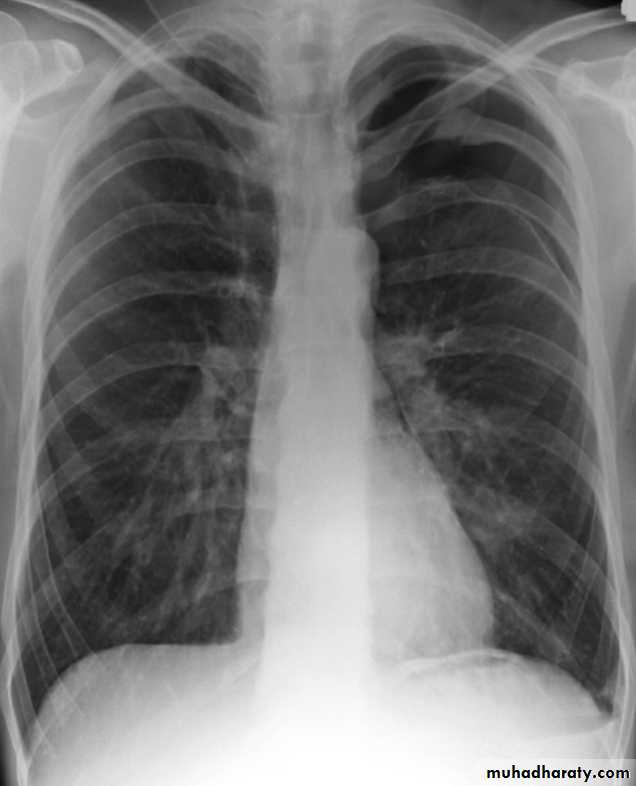

Pneumothorax

Pneumothorax refers to the presence of gas (air) in the pleural space. When this collection of gas is constantly enlarging with resulting compression of mediastinal structures it can be life-threatening and is known as a tension pneumothoraxIt is useful to divide pneumo thoraces into three categories :

Radiographic features

Chest radiographA pneumothorax is, when looked for, usually relatively easily appreciated. Typically they demonstrate:

visible visceral pleural edge see as a very thin, sharp white line

no lung markings are seen peripheral to this line

the peripheral space is radiolucent compared to adjacent lung

the lung may completely collapse

the mediastinum should not shift away from the pneumothorax unless a tension pneumothorax is present